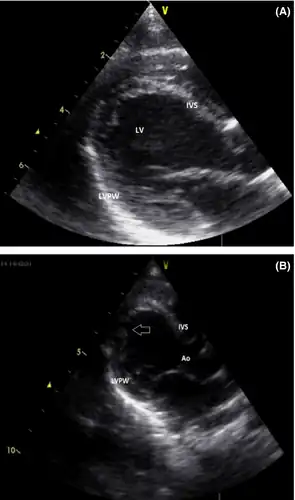

The signs and symptoms of this disorder typically appear in early childhood. Almost all affected children have delayed development. Additional signs and symptoms can include weak muscle tone (hypotonia), seizures, diarrhea, vomiting, and low blood sugar (hypoglycemia). A heart condition called cardiomyopathy, which weakens and enlarges the heart muscle, is another common feature of malonyl-CoA decarboxylase deficiency.

Some common symptoms in Malonyl-CoA decarboxylase deficiency, such as cardiomyopathy and metabolic acidosis, are triggered by the high concentrations of Malonyl-CoA in the cytoplasm. High levels of Malonyl-CoA will inhibit β-oxidation of fatty acids through deactivating the carrier of fatty acyl group, CPT1, and thus, blocking fatty acids from going into the mitochondrial matrix for oxidation.[2]